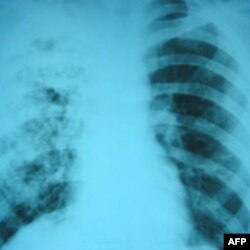

Snimak pluća pacijenta sa tuberkolozom